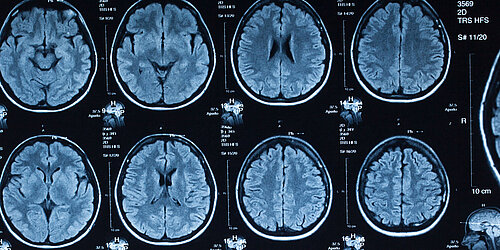

Das KI-Leuchtturmprojekt KI-INSPIRE entwickelt KI-basierte Verfahren, die die Strahlendosis in der medizinischen Bildgebung reduzieren sollen. Projektkoordinator Prof. Christoph Hoeschen, Universität Magdeburg, berichtete uns über die Methoden.

Hoeschen: Strahlenbasierte Verfahren wie etwa die Computertomographie sind in der Diagnostik und der minimalinvasiven Therapie wichtig, um ein Bild von medizinischen Gegebenheiten zu erhalten und Patient*innen passend zu behandeln. Allerdings ist damit auch eine Strahlenexposition verbunden, für Patient*innen ebenso wie für das medizinische Personal. Unser Verfahren in KI-INSPIRE kann so die potenziell schädliche Strahlendosis maßgeblich reduzieren. Das ist für mich genau der richtige Bereich, um KI anzuwenden: Dort, wo es Menschen direkt hilft.

Wir verbessen die Bildqualität bei gleichzeitig weniger verwendeten Rohdaten. Bei der Intervention werden immer wieder die gleichen Bereiche im Bild aufgenommen, zeitgleich wird eine Nadel oder ein Katheter eingeführt. Das bedeutet: Sie haben ganz viele Vorabinformationen. Und diese Informationen kann ich durch eine KI in die folgenden Bilder integrieren lassen. Dann brauche ich dafür keine Live-Aufnahmen und somit auch eine geringere Strahlendosis. Und die KI-Algorithmen filtern bei der Verarbeitung der Rohdaten Störungen heraus. So entstehen Bilder mit einer höheren Abbildungsschärfe. Das erfolgt live, die Daten werden online bereitgestellt, die Ärztin oder der Arzt sieht das direkt auf dem Bildschirm.

Wir hatten uns vorgenommen, dass wir die exponentielle Strahlendosis der Patient*innen um zwei Drittel senken. Dieses ambitionierte Ziel haben wir erreicht. Wir haben mit den erprobten Verfahren die gemessene Strahlung um zwei Drittel reduziert, teilweise sogar noch mehr. Wir haben so gezeigt, dass KI-Verfahren zur Dosisreduktion für interventionelle Bildgebung wirklich Sinn machen und Erfolg versprechen. Darüber hinaus haben wir auch die Reduktion von Störsignalen durch z. B. Metalle im Körper, sogenannte Artefakte, die Streustrahlenreduktion aber auch die Entwicklung von Verfahren zum Testen von KI-Methoden im klinischen Alltag vorangebracht.

CT Aufnahmen eines menschlichen Gehirns